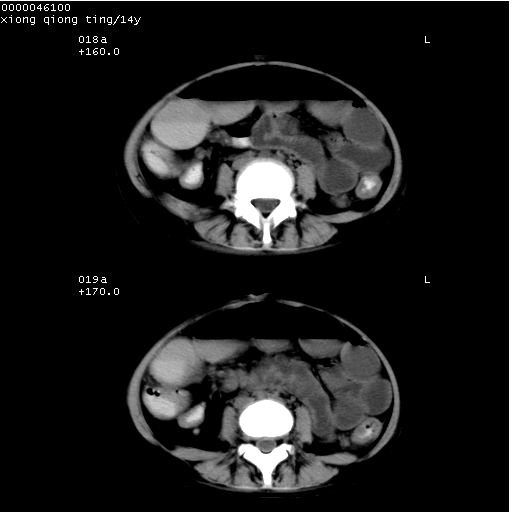

患儿 女,14岁。不规则发热一周,偶感头痛,无抽搐及呕吐。pe:神清,精神差,双侧瞳孔等大等圆,对光反射敏感,双肺未闻及明显啰音,心音有力,腹部触之似揉面感,下腹压痛,无反跳痛。

腹部b超提示:子宫缩小,盆腔积液,肝实质回声密集。

临床诊断:发热原因待查:1)腹部结核感染。2)伤寒?3)结缔组织病?

中下腹及盆腔ct轴位平扫+增强扫描(层厚10mm,螺距1.0,重建间隔10mm),图像如下:

(注:患儿检查当日上午9时口服胃肠道对比剂,下午3时许行ct扫描检查,未行对比剂直肠保留灌肠,检查当日患儿腹泻)

中下腹及盆腔ct轴位扫描(ps+ce)提示:腹部肠管明显充气扩张,并见数个不同宽度之气液平面;疑不全性肠梗阻或肠郁张。临床会诊考虑为患儿腹泻,肠郁张所致;后来未经特殊处理,患儿大便恢复正常,亦无腹胀。

临床出院诊断:1)结核性腹膜炎。2)腹膜后淋巴结结核。3)脂肪肝。